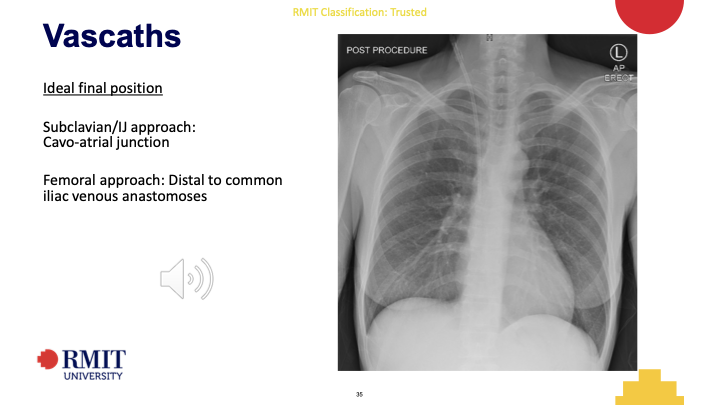

Vascath Ideal final position

Subclavian/IJ approach:

Cavo-atrial junction

Femoral approach: Distal to common

iliac venous anastomoses